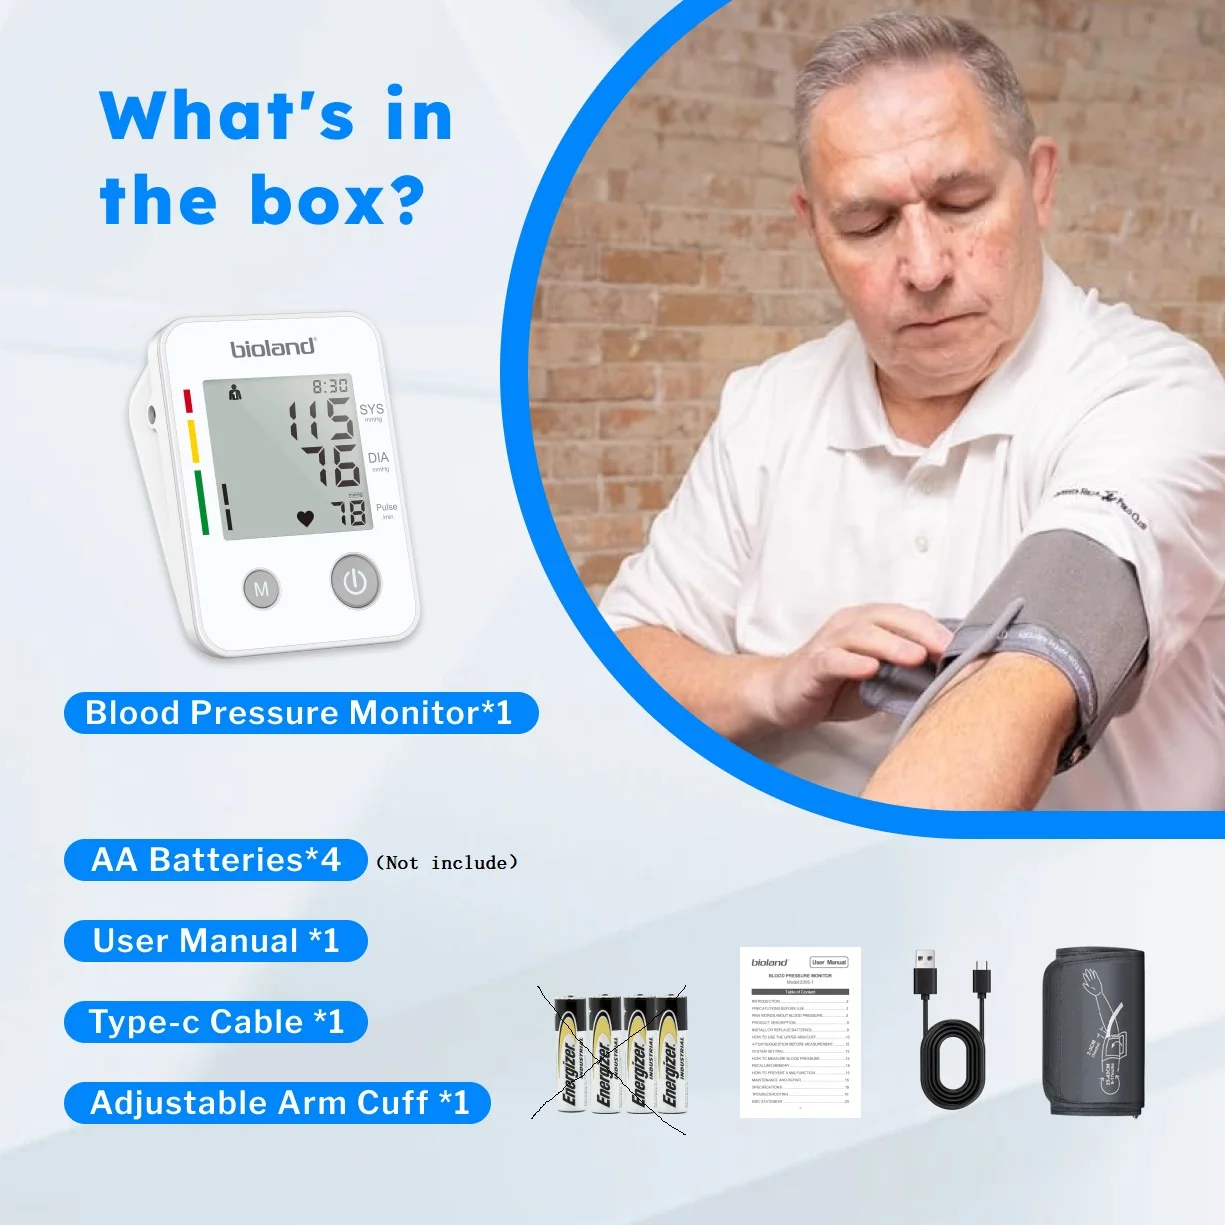

Application: Arm

Blood Pressure Monitor: Blood Pressure Measuring device,blood pressure gauge,digital tensiometers,Tensiometer blood pressure,Heart Rate Monitor,Blood pressure meter,Blood pressure smartwath,medical tensiometer,presion arterial monitor

Bluetooth: No

Brand Name: bioland

Certification: CE

Choice: yes

Data Storage: Yes

Function: Blood Pressure Monitor

Hign-concerned Chemical: None

Indication: Digital LCDDISPLAY

Is Batteries Included: No

Item Type: blood pressure

Material: ABS

Memory: 2*120 sets

Model Number: 2005&2005-1

Origin: CHINA

Size: 1pc

semi_Choice: yes

voice: Y

Recommend: The one for blood glucose meter, if you like kindly go to check it

Bioland Blood Pressure Monitor 2005 Tensiometer Upper Arm Automatic Digital BP Measuring Device Blood Pressure guage kit 2005-1

Reminder:

Due to traffic limitation the battery not included, kindly note.

【Safe and reliable】

Boasting specific algorithms & chip, each individually-tested Bioland BP Monitor will provide you with the most trustworthy readings, helping you track your health easily at home. A safe and reliable BP-machine to our families.

【Large LED Display】

The large LED display with clear and oversized numbers, makes it easy to read your real-time blood pressure and pulse rate. High precision chip of large LED touch screen provides clinically accurate readings, giving the most exact systolic, diastolic pressure and pulse rate data by one touchable button and easy to read the backlist screen with multi-colored LED indicator lights.

【120 Memory for 2 Users】

This BP unit can monitor 2 users together, store 120 readings with date & time stamps for each displays the average of last 3 readings, includes irregular heartbeat detection. Helps users to easily track their health, blood pressure and heart rate according to the specific time and date.

Reasons of monitoring blood pressure everyday:

1. Keep abreast of your own physical condition and avoid unnecessary risks

2. Monitor your body's blood pressure changes, helping doctors getting to know your medical history more accurately and quickly

Features:

1.HD screen display;High quality acrylic lenses

2.Irregular heartbeat detection (IHB function)

3.Blood pressure classification (WHO) indicator

4.2*120 groups memory function

5.Cuff tightness detection (22-42cm cuff)

6.Smart pressure; Overvoltage protection

7.Voice reporting(With English talking voice)

8.Low power prompt

9.Average of last 3 Memories

【Blood Pressure&Heartbeat Indicator】

A coded indicator for blood pressure. The irregular heartbeat symbol will show up when an irregular heartbeat is detected. When a specific error occurs in the product, the cause of the error can be determined by comparing the error symbol with the manual.

How to use it:

Wear the arm cuff

Make the nozzle of the arm cuff point to your forearm,arm cuff is 1-2cm higher than the elbow joint.Red-marked area on the arm cuff point to your mid-finger,please keep the nozzle upwards.

Measuring Condition:

1.Keep back straight, relax

2.Expose your upper arm or wear thin clothe only